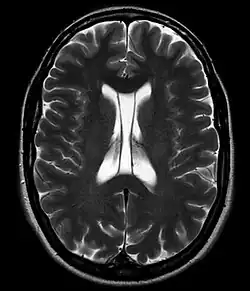

В большинстве случаев наличие полости не оказывает какого-либо клинически значимого влияния на человека.

В то же время отмечается некоторое увеличение частоты встречаемости полости прозрачной перегородки у пациентов с шизофренией[6], посттравматическим стрессовым расстройством[7], черепно-мозговой травмой[8], а также диссоциальным расстройством личности[3]. Наличие расширенной полости — один из отличительных признаков пациентов с травматической энцефалопатией боксеров (dementia pugilistica).[9]